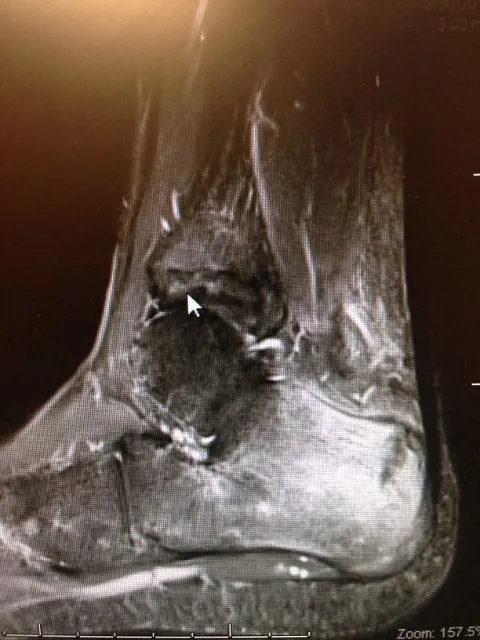

MRI imaging is excellent for diagnosing stress fractures. A T1 weighted image will show normal bone in a white color and edema and/or fracture lines in gray to black color (below left). T2 weighted imaged are the opposite and will show bone black and any fluid like swelling within the bone or throught a fracture as white (below right).